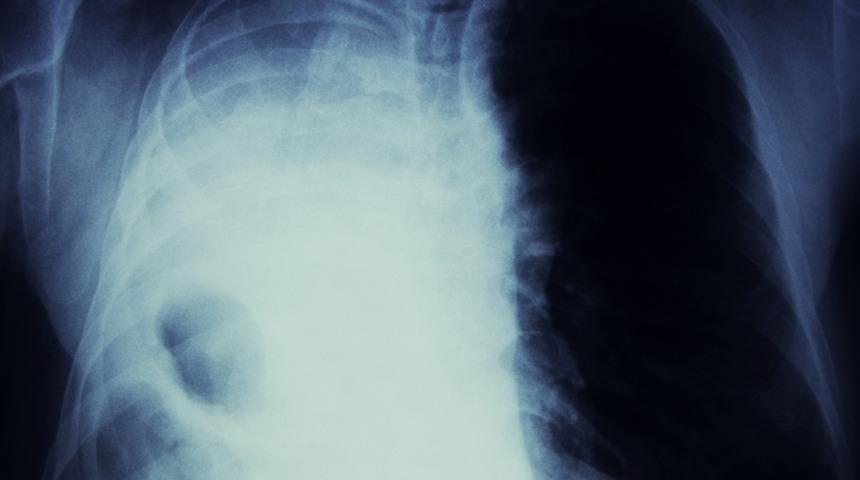

Akciğer kanseri nedenleri denilince sıralanan 6 maddeye dikkat çeken Onkoloji Uzmanı Prof. Dr. Aziz Yazar, kansere bağlı ölümlerin başında yer alan akciğer kanserinden korunmak için yapılması gerekenleri anlattı. Her yıl mutlaka akciğer taraması yapılması gerektiğini anlatan Yazar, erken teşhisin akciğer kanseri tedavisinde önemli rol oynayabileceğini söyledi.

Akciğer kanseri tüm dünyada ve ülkemizde kansere bağlı ölümlerde birinci sırada yer alıyor. Dünyada her yıl yaklaşık 1.6 milyon ve ülkemizde de yaklaşık 30 bin kişi akciğer kanseri nedeniyle hayatını kaybediyor. Akciğer kanserine bağlı ölümlerin yüksek olmasının nedeni ise teşhisin genellikle ileri evrelerde konulması. Öyle ki hastaların yaklaşık yüzde 70’inde kanser 3 veya 4’üncü evreye ulaştığında tespit ediliyor. Bunun nedeni ise akciğer kanserine özgü bir belirtinin olmaması ve bazen de hastaların akciğer kanserine bağlı olabilecek bazı belirtileri dikkate almamaları. Oysa günümüzde tedavide yaşanan çok önemli gelişmeler sayesinde, akciğer kanserine erken tanı konulduğunda hastalar uzun yıllar sağlıklı bir yaşam sürebiliyorlar!

Acıbadem Altunizade Hastanesi Tıbbi Onkoloji Uzmanı Prof. Dr. Aziz Yazar, yüksek risk faktörüne sahip kişilerde düzenli yapılan akciğer taramalarının akciğer kanserinin erken evrede teşhis edilmesinde kilit rol üstlendiklerine dikkat çekerek, “Düşük doz bilgisayarlı tomografi ile yapılan düzenli akciğer taraması sayesinde; öksürük, kanlı balgam, kilo kaybı ve ağrı gibi hiçbir şikayeti olmayan kişilerde akciğer kanserini erken evrede saptamak mümkün olabiliyor. Bu nedenle 55-77 yaş aralığında olan, yılda 30 paket veya daha fazla sigara içen ya da son 15 yılda sigarayı bırakan kişilerin yılda bir kez akciğer kanseri taramasından geçmeleri yaşamsal öneme sahip” diyor.